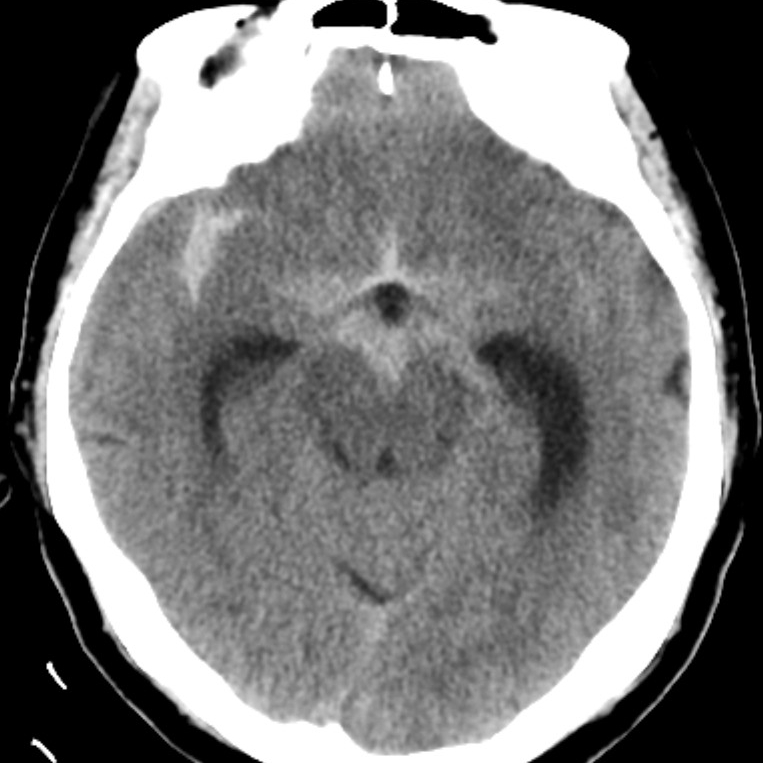

病例一为77岁女性患者,既往高血压病史。因“突发剧烈头痛伴恶心2天”前来清华大学附属垂杨柳医院急诊科就诊。头颅CT检查提示蛛网膜下腔出血,头颈动脉CTA提示右侧大脑中动脉M1段分叉处宽颈动脉瘤。神经外科脑血管病介入团队急诊为患者实施了全脑血管造影术(DSA),造影显示动脉瘤不规则,可见子囊,宽颈,主要累及下干。团队采取了支架辅助弹簧圈栓塞术,患者颅内“不定时炸弹”被成功拆除。动脉瘤达到致密栓塞,载瘤动脉通畅。住院半个月后顺利出院,无神经功能障碍。

▲头颅CT显示蛛网膜下腔出血